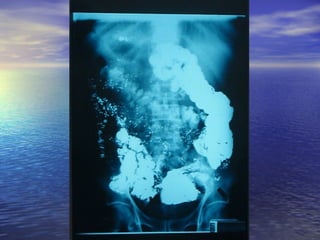

• 1.- CALIBRE: Dilución = obstrucción1.- CALIBRE: Dilución = obstrucción distal, enf.distal, enf.

Celiaca,Celiaca, whipple, linfosarcomawhipple, linfosarcoma

• 2.- ESTENOSIS: Enf. De Crohn, linfosarcoma,2.- ESTENOSIS: Enf. De Crohn, linfosarcoma,

tuberculosis, invasión por tumores cercanostuberculosis, invasión por tumores cercanos

del páncreas, colon.del páncreas, colon.

• 3.- DEFECTOS DE LLENADO: Pólipos ,Sx. Peutz-3.- DEFECTOS DE LLENADO: Pólipos ,Sx. Peutz-

Jegher,Jegher, poliposis familiar, enf. De Crohn, linfomas ypoliposis familiar, enf. De Crohn, linfomas y

metástasis.metástasis.

• 4.- DIVERTICULOSIS: Diverticulosis yeyunal, pseudo-4.- DIVERTICULOSIS: Diverticulosis yeyunal, pseudo-

divertículos (Crohn, esclerosis sistémica)divertículos (Crohn, esclerosis sistémica)